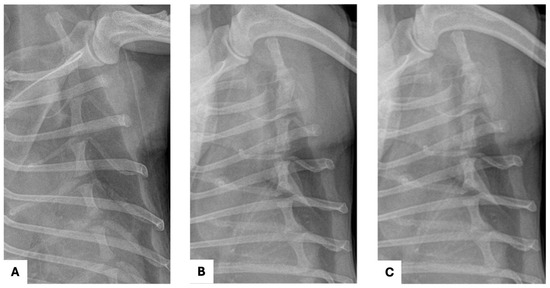

A 10-year-old castrated male Chihuahua weighing 3.06 kg was presented with a chronic, progressively worsening cough of five months’ duration. Diagnostic imaging, including thoracic radiography and computed tomography, identified a well-defined cranial mediastinal mass consistent with a thymic tumor. Surgical excision was performed via median sternotomy with complete thymectomy. Following tumor removal, sternal closure was achieved using a non-absorbable ultra-high-molecular-weight polyethylene (UHMWPE) suture material (FiberWire®, Arthrex, Naples, FL, USA). Histopathological examination confirmed the diagnosis of an epithelial-predominant thymoma with narrow but complete surgical margins. Postoperative recovery was uneventful, and the dog was discharged three days after surgery. Clinical signs, including coughing, progressively improved during follow-up. Radiographic evaluation performed up to postoperative day 57 demonstrated stable sternal alignment without evidence of dehiscence, implant-related complications, or disease recurrence. This report describes the first clinical case of FiberWire use for median sternotomy closure following thymectomy in a dog. The favorable clinical and radiographic outcomes observed during postoperative follow-up suggest that FiberWire may represent a viable alternative to traditional stainless-steel wire for sternal fixation in canine thoracic surgery. Full article